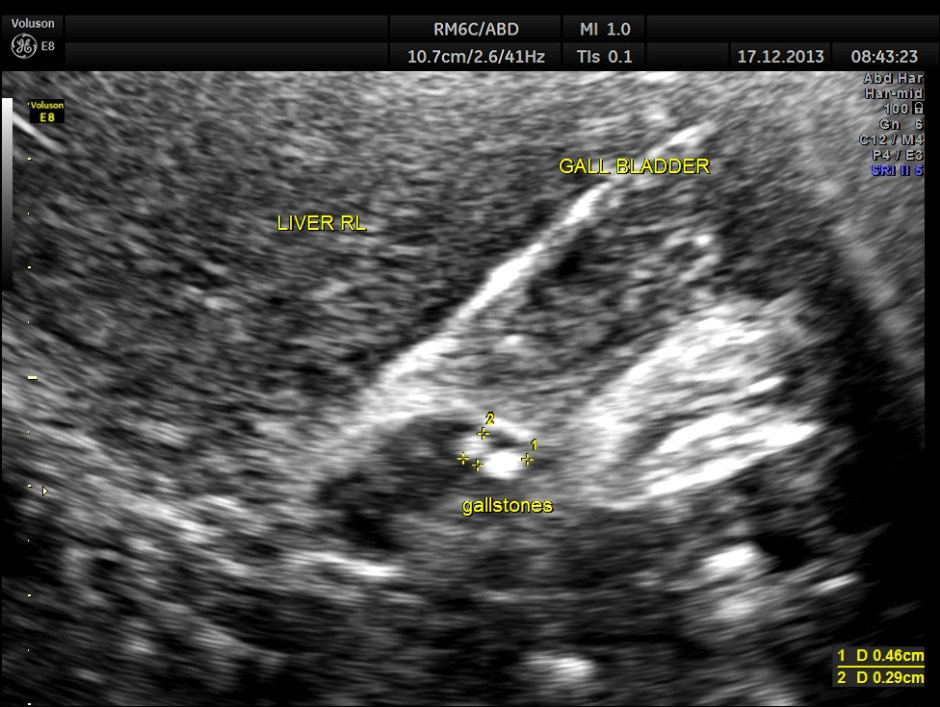

This was a 63-year-old gentleman who came for recurrent episodic right upper quadrant pain of 2 to 3 weeks duration.On examination Murphy’s sign was positive. The pictures follow.

ACUTE CHOLECYSTITIS WITH MULTIPLE SMALL GALLSTONES AND ECHOGENIC SLUDGE WAS SEEN.

The Common Bile Duct is 5.07 mms.